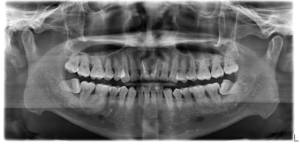

2026 香港杜牙根治療細節:一文看清程序、活髓治療分別及成功因素分析 當牙齒出現嚴重蛀牙或疼痛

2026 香港杜牙根失敗風險與後遺症分析:牙痛、牙瘡再現應如何處理? 如果牙齒蛀得太嚴重,患者通常有兩個選擇: